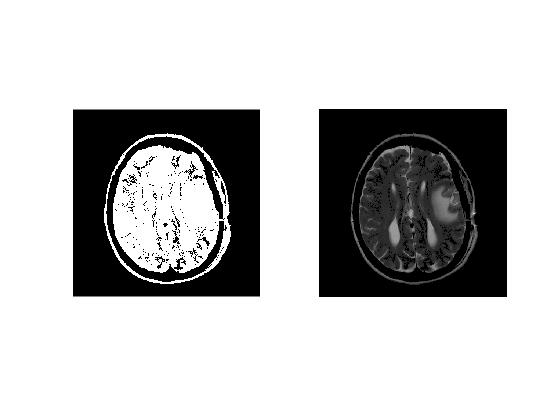

Cleaning Binary Mask

We use 'bwareaopen' to remover all isolated regions of size 500 or less.

% clean mask of small areas

cleanBW = bwareaopen(normBW,500);

% Displaying binary mask

figure

subplot(1,2,1)

imagesc(cleanBW); colormap('gray')

% Displaying selected ROI

subplot(1,2,2)

imagesc(double(cleanBW).*normMriImage1);colormap('gray');

A summary of semi-automatic brain extraction pipeline is presented in the montage below.